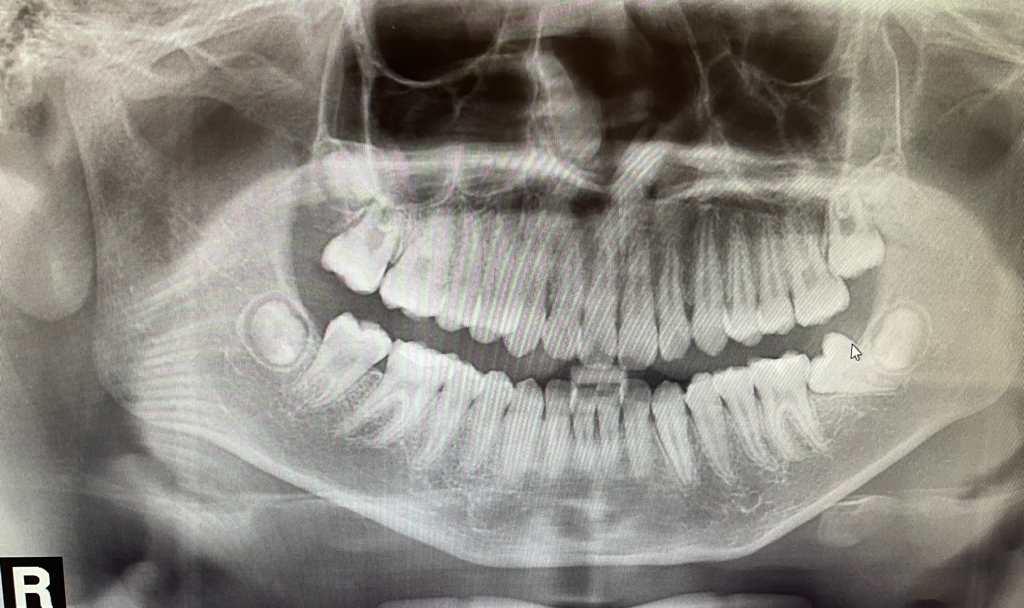

어금니가 옆으로 누워서 자라고 있는데 교정되나요?

14살 자녀가 있습니다.

잇몸이 아파서 치과에가서 엑스레이 찍었습니다.

오른쪽 사진 보시면 아래 어금니는 옆으로 누워있습니다.

윗 어금니는 옆에 치아를 누루고 있습니다.

2번째 어금니가 누워서 나고 있지만 뒤에 있는 사랑니 빼고 어금니를 바로 세우는 것이

가능할 것으로 보입니다.

정확한 비용은 교정치과에서 상담을 받아보시는게 좋을것같습니다. 빨리 치료를 받으시는게 좋을것같습니다. 치아가 쓰러져 잇어서 앞치아가 썩을 가능성이 높아 보입니다.

현재 사진 자료만으로는 교정으로 해당 치아를 upright 시킬 수 있는지 알 수는 없습니다. 다만 통상적으로 이러한 상태라면 교정이 가능할 것으로 보입니다. 물론 정확한 판단을 위해서는 임상사진 및 방사선 계측 자료 등이 모두 필요합니다. 비용은 치과마다 다를 수 있기 때문에 교정치과 방문 후 상담이 필요합니다.